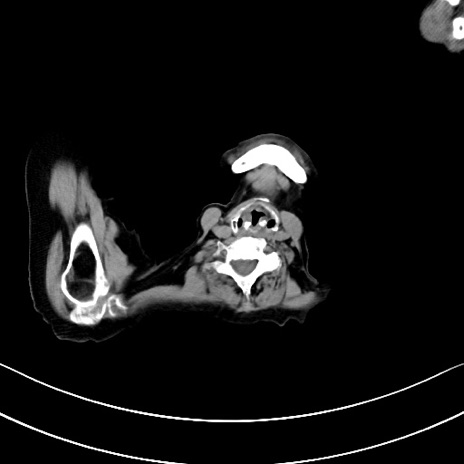

症例40(横断像)他院1日前

横断像

他院CT